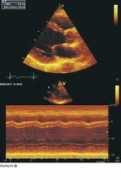

Top Images for Teichholz